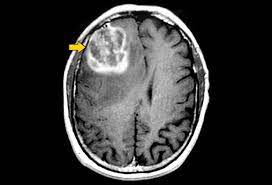

Brain tumour is one of the most dangerous diseases which require early and accurately detection methods. And brain tumour is a cancerous or non-cancerous mass or growth of abnormal cells in the brain. Now most detection and diagnosis methods depend on decision of neurospecialists, and radiologist for image evaluation which possible to human errors and time consuming. The main purpose of this project is to build a robust CNN model that can classify if the subject has a tumour or not based on Brain MRI scan images with an acceptable accuracy for medical grade application

To implement this project we are using 4 different images and this images are called as FLAIR, T1, T2 and T1CE and the label segmented image. The multi-institutional dataset, acquired from 19 different contributors, contains multimodal MRI scans of each patient, namely T1, T1 contrast-enhanced (T1ce), T2-weighted (T2), and Fluid Attenuated Inversion Recovery (FLAIR), from which the tumour sub regions are segmented. The data is processed to overcome discrepancies such that they are skull-stripped

To automate brain tumour segmentation process author is combining both 3D CNN and UNET algorithms as deep learning is gaining popularity in efficient semantic segmentation of medical images. To further enhance segmentation process author is using combination or ensemble of two deep learning algorithms called CNN and UNET. Both algorithms trained separately on BRATS brain tumour dataset and then predicted output of both algorithms will be merge or map to generate final segmentation and the output generated is giving high dice score after mapping both algorithms segmentation and then predicting final segmented output. Dice score refers to correctly mapping of segmented parts in the image . The task is to develop an automated brain tumour segmentation method, for successful delineation of tumours into intra tumour classes with improved efficiency and accuracy in comparison to existing methods.

Automated segmentation of brain tumour from multimodal MR images is pivotal for the analysis and monitoring of disease progression. As gliomas are malignant and heterogeneous, efficient and accurate segmentation techniques are used for the successful delineation of tumours into intra tumour classes. Deep learning algorithms outperform on tasks of semantic segmentation as opposed to the more conventional, context-based computer vision approaches. Extensively used for biomedical image segmentation, Convolutional Neural Networks have significantly improved the state-of-the-art accuracy on the task of brain tumour segmentation. In this paper, we propose an ensemble of two segmentation networks: a 3D CNN and a U-Net, in a significant yet straightforward combinative technique that results in better and accurate predictions. Both models were trained separately on the BraTS-19 challenge dataset and evaluated to yield segmentation maps which considerably differed from each other in terms of segmented tumour sub-regions and were ensembled variably to achieve the final prediction